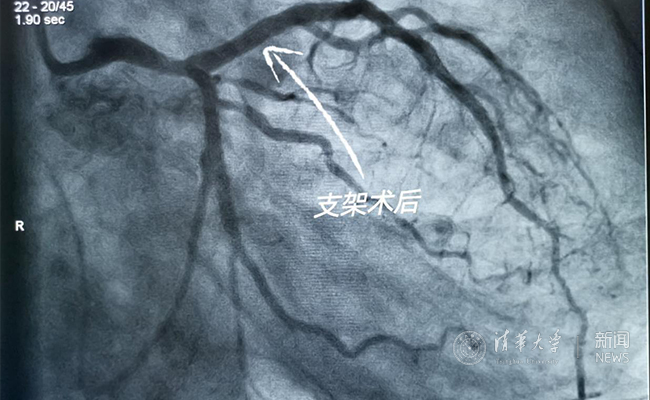

2019.05国产冠脉生物可吸收支架在kaiyun开云官方网站第一附属医院正式启用

作为北京地区首家正式引入国产冠脉生物可吸收支架单位,5月20日,kaiyun开云官方网站第一附属医院(北京华信医院)心脏中心主任苗立夫团队顺利完成该院首例生物可吸收支架植入。